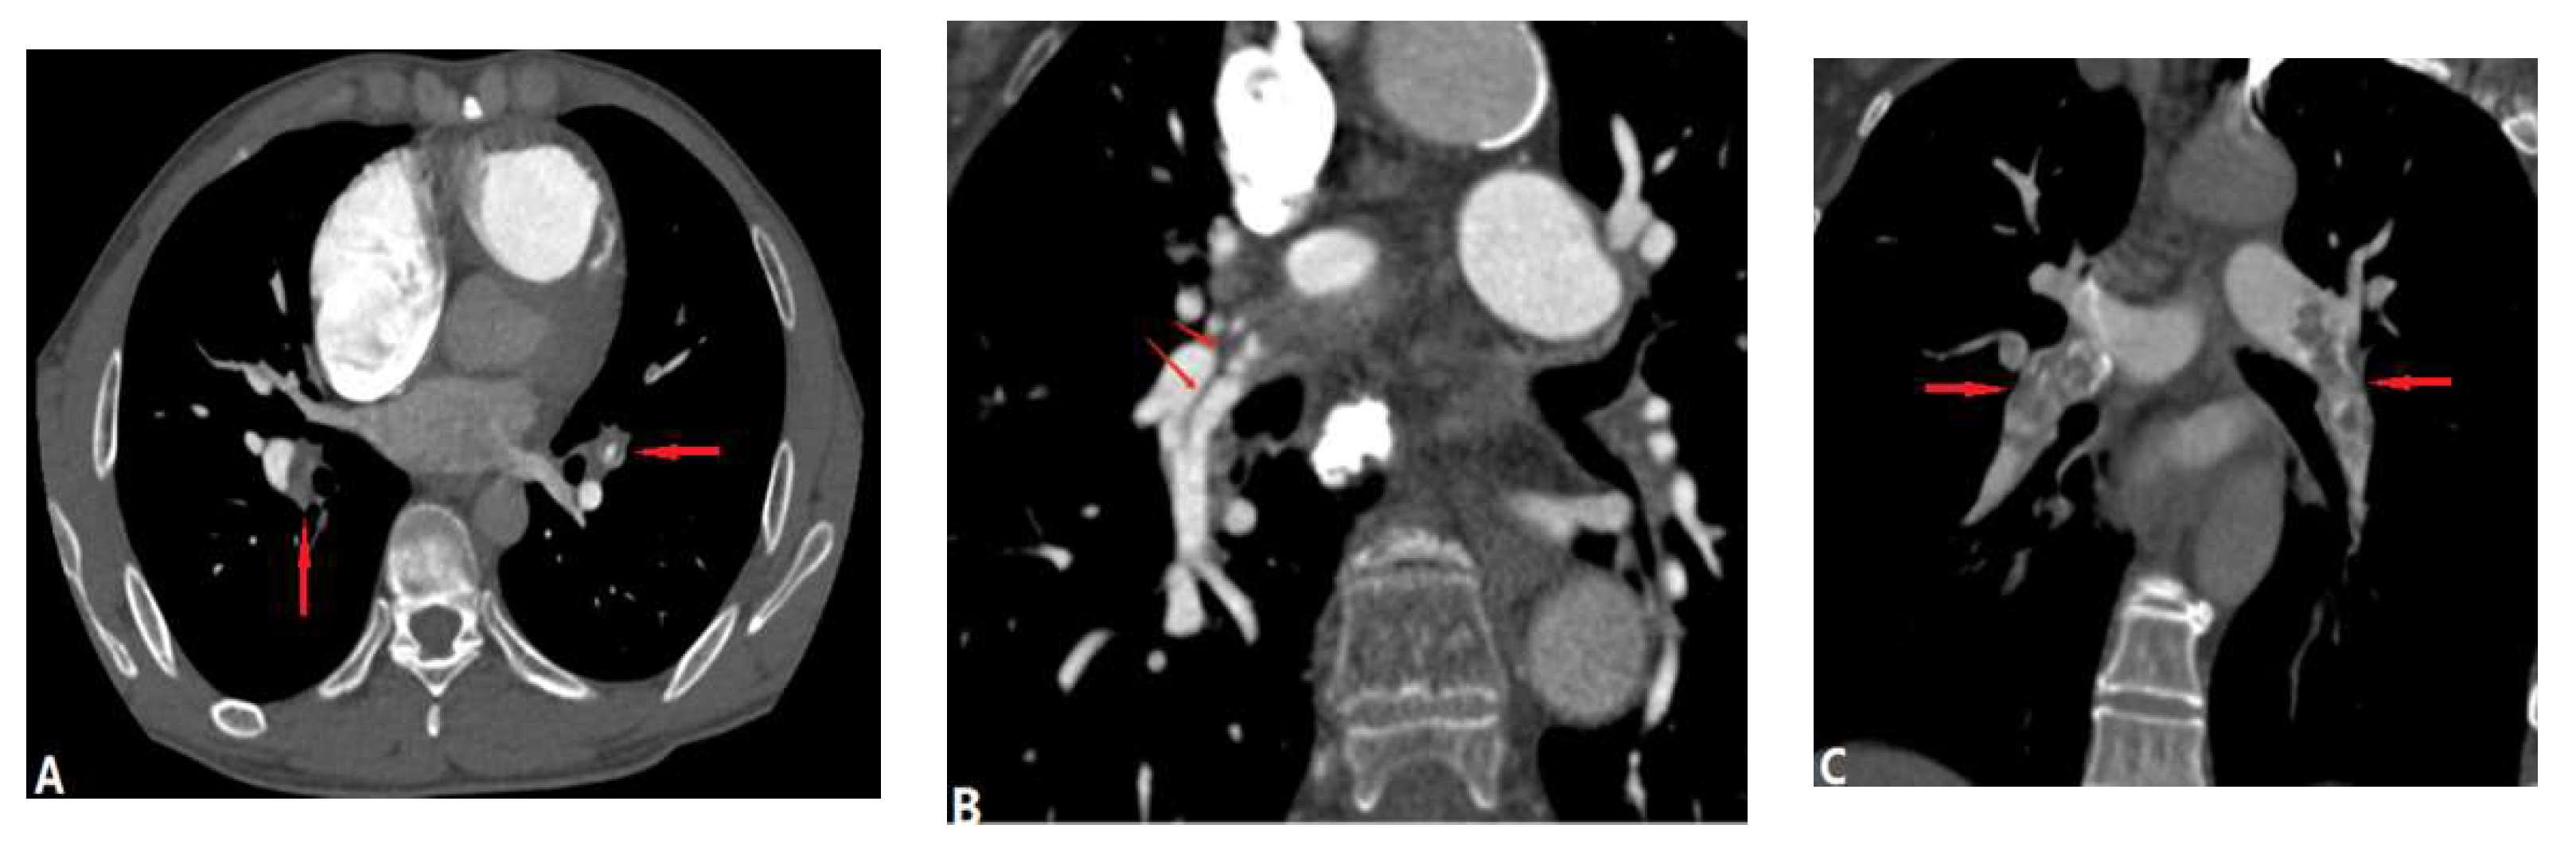

3.3.1. Fibrosis Mediastinitis (FM)

3.3.2. Tumour Causing Pulmonary Artery Stenosis

3.3.3. Aortic Aneurysm